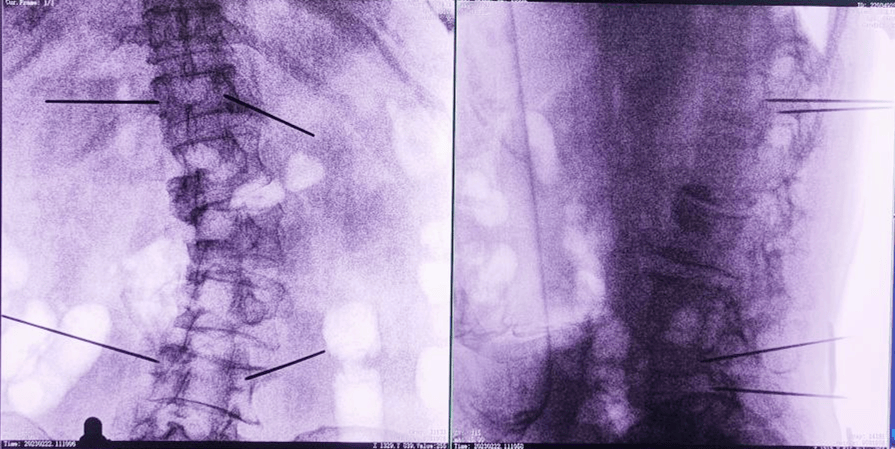

術(shù)中,手術(shù)團隊先對患者進行三維影像掃描,將圖像同步傳輸至機器人成像系統(tǒng)后,利用骨科手術(shù)機器人導(dǎo)航系統(tǒng)做好手術(shù)規(guī)劃,隨后利用其機械臂,將手術(shù)工具精確定位到“目的地”,鋪好“通道”,這就很好的解決了醫(yī)生“盲穿”的問題。

主任為患者注射骨水泥,再次影像掃描后,發(fā)現(xiàn)骨水泥進入位置非常好,彌散效果更佳,手術(shù)順利完成,患者的恢復(fù)也自然更好。